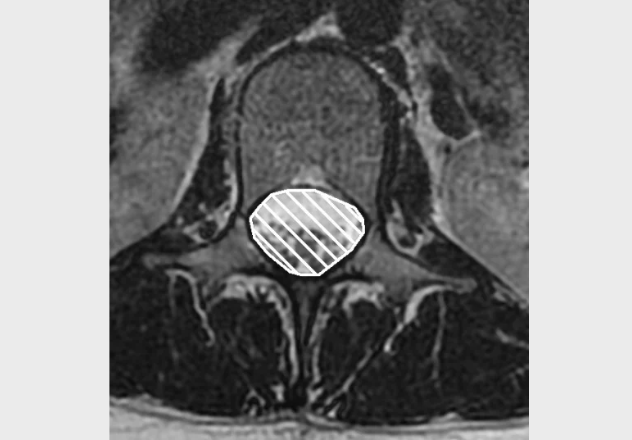

• The two main types of lumbar spine stenosis are Foraminal Stenosis (claudicant neuropathic leg pain or nerve root compression) and Central Canal Stenosis.

• Stenosis occurs as a result of spondylosis.  Normal degenerative changes of the spine include reduction in disc height, thickening of surrounding ligaments (ligamentum flavum), and development of bony spurs or osteophytes; all of which could reduce foraminal or central canal spaces and possibly cause symptoms.